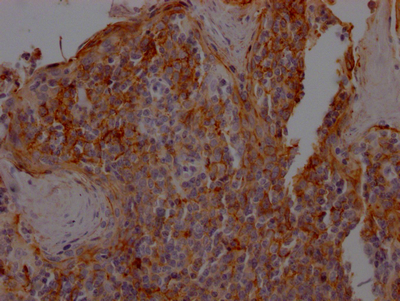

IHC (Immunohiostchemistry)

(IHC image diluted at 1:100 and staining in paraffin-embedded human lung cancer performed on a Leica BondTM system. After dewaxing and hydration, antigen retrieval was mediated by high pressure in a citrate buffer (pH 6.0). Section was blocked with 10% normal goat serum 30min at RT. Then primary antibody (1% BSA) was incubated at 4 degree C overnight. The primary is detected by a Goat anti-rabbit IgG polymer labeled by HRP and visualized using 0.05% DAB.)